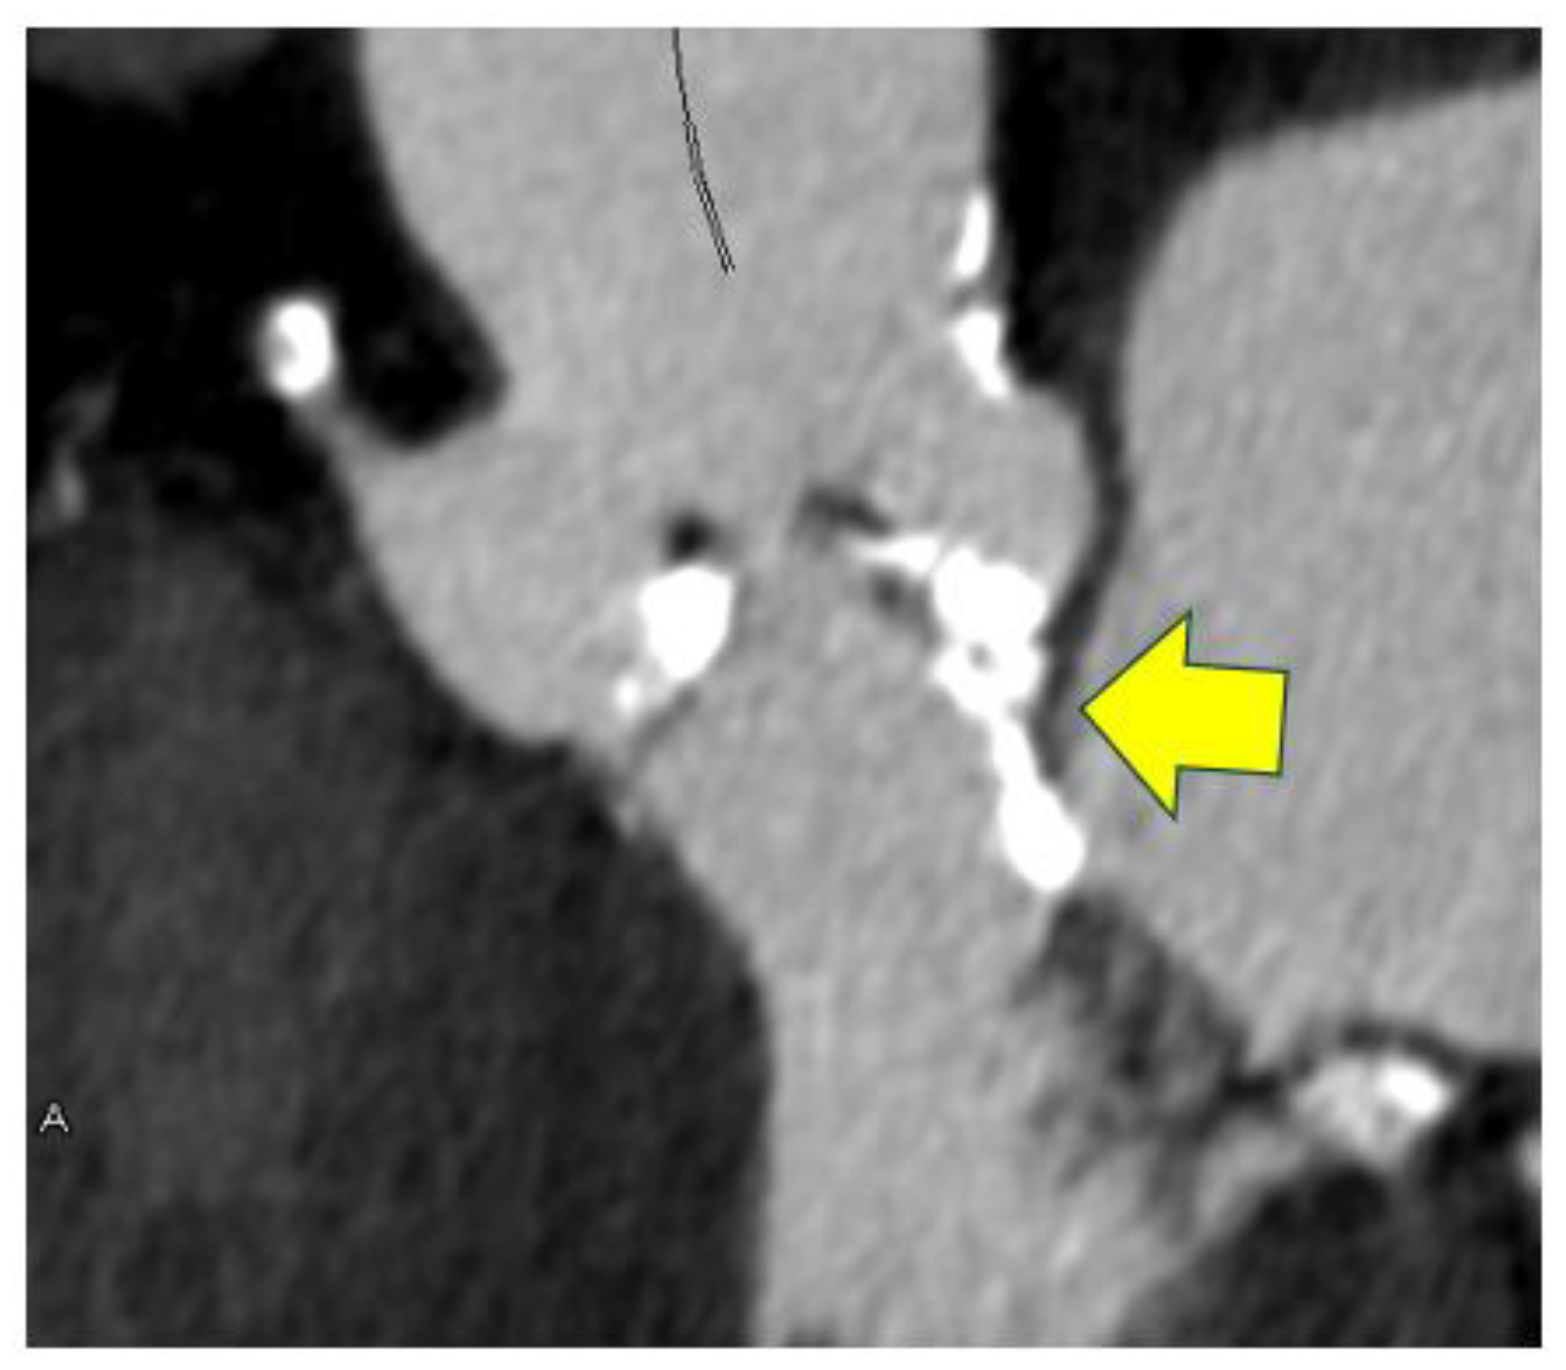

- Saito, Y.; Takaoka, H.; Funabashi, N.; Ozawa, K.; Tamura, Y.; Saito, M.; Matsumiya, G.; Kobayashi, Y. A case of very severe aortic stenosis due to unicuspid aortic valve mimicking bicuspid aortic valve with calcification on cardiac computed tomography. Int. J. Cardiol. 2016, 215, 516–518. [Google Scholar] [CrossRef]